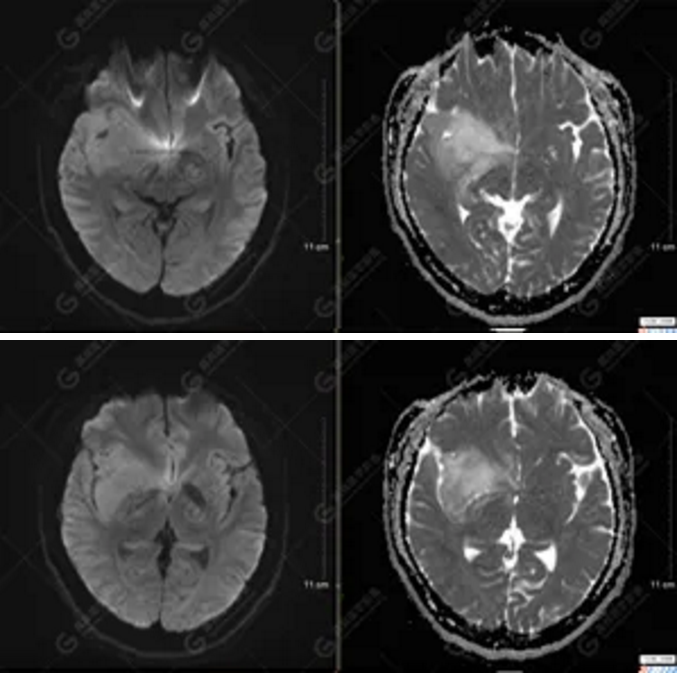

【MRI平掃及增強(qiáng)檢查所見(jiàn)】右側(cè)額顳島葉、右側(cè)海馬及右側(cè)基底節(jié)區(qū)見(jiàn)一團(tuán)塊狀異常信號(hào)影,累及右側(cè)下丘腦及視交叉,大小約5.1cm×4.5cm×4.3cm,呈長(zhǎng)T1長(zhǎng)T2信號(hào),F(xiàn)LAIR序列呈等、稍高信號(hào),DWI序列呈稍高信號(hào),ADC圖高信號(hào),增強(qiáng)后無(wú)明顯強(qiáng)化;病灶周?chē)?jiàn)片狀長(zhǎng)T1長(zhǎng)T2水腫信號(hào)影,F(xiàn)LAIR序列呈高信號(hào),病灶內(nèi)見(jiàn)右側(cè)大腦中動(dòng)脈穿行。余腦實(shí)質(zhì)內(nèi)未見(jiàn)局灶性信號(hào)異常,增強(qiáng)后未見(jiàn)異常強(qiáng)化。右側(cè)側(cè)腦室輕度受壓,余腦室、腦池大小、形態(tài)均正常,中線(xiàn)結(jié)構(gòu)居中